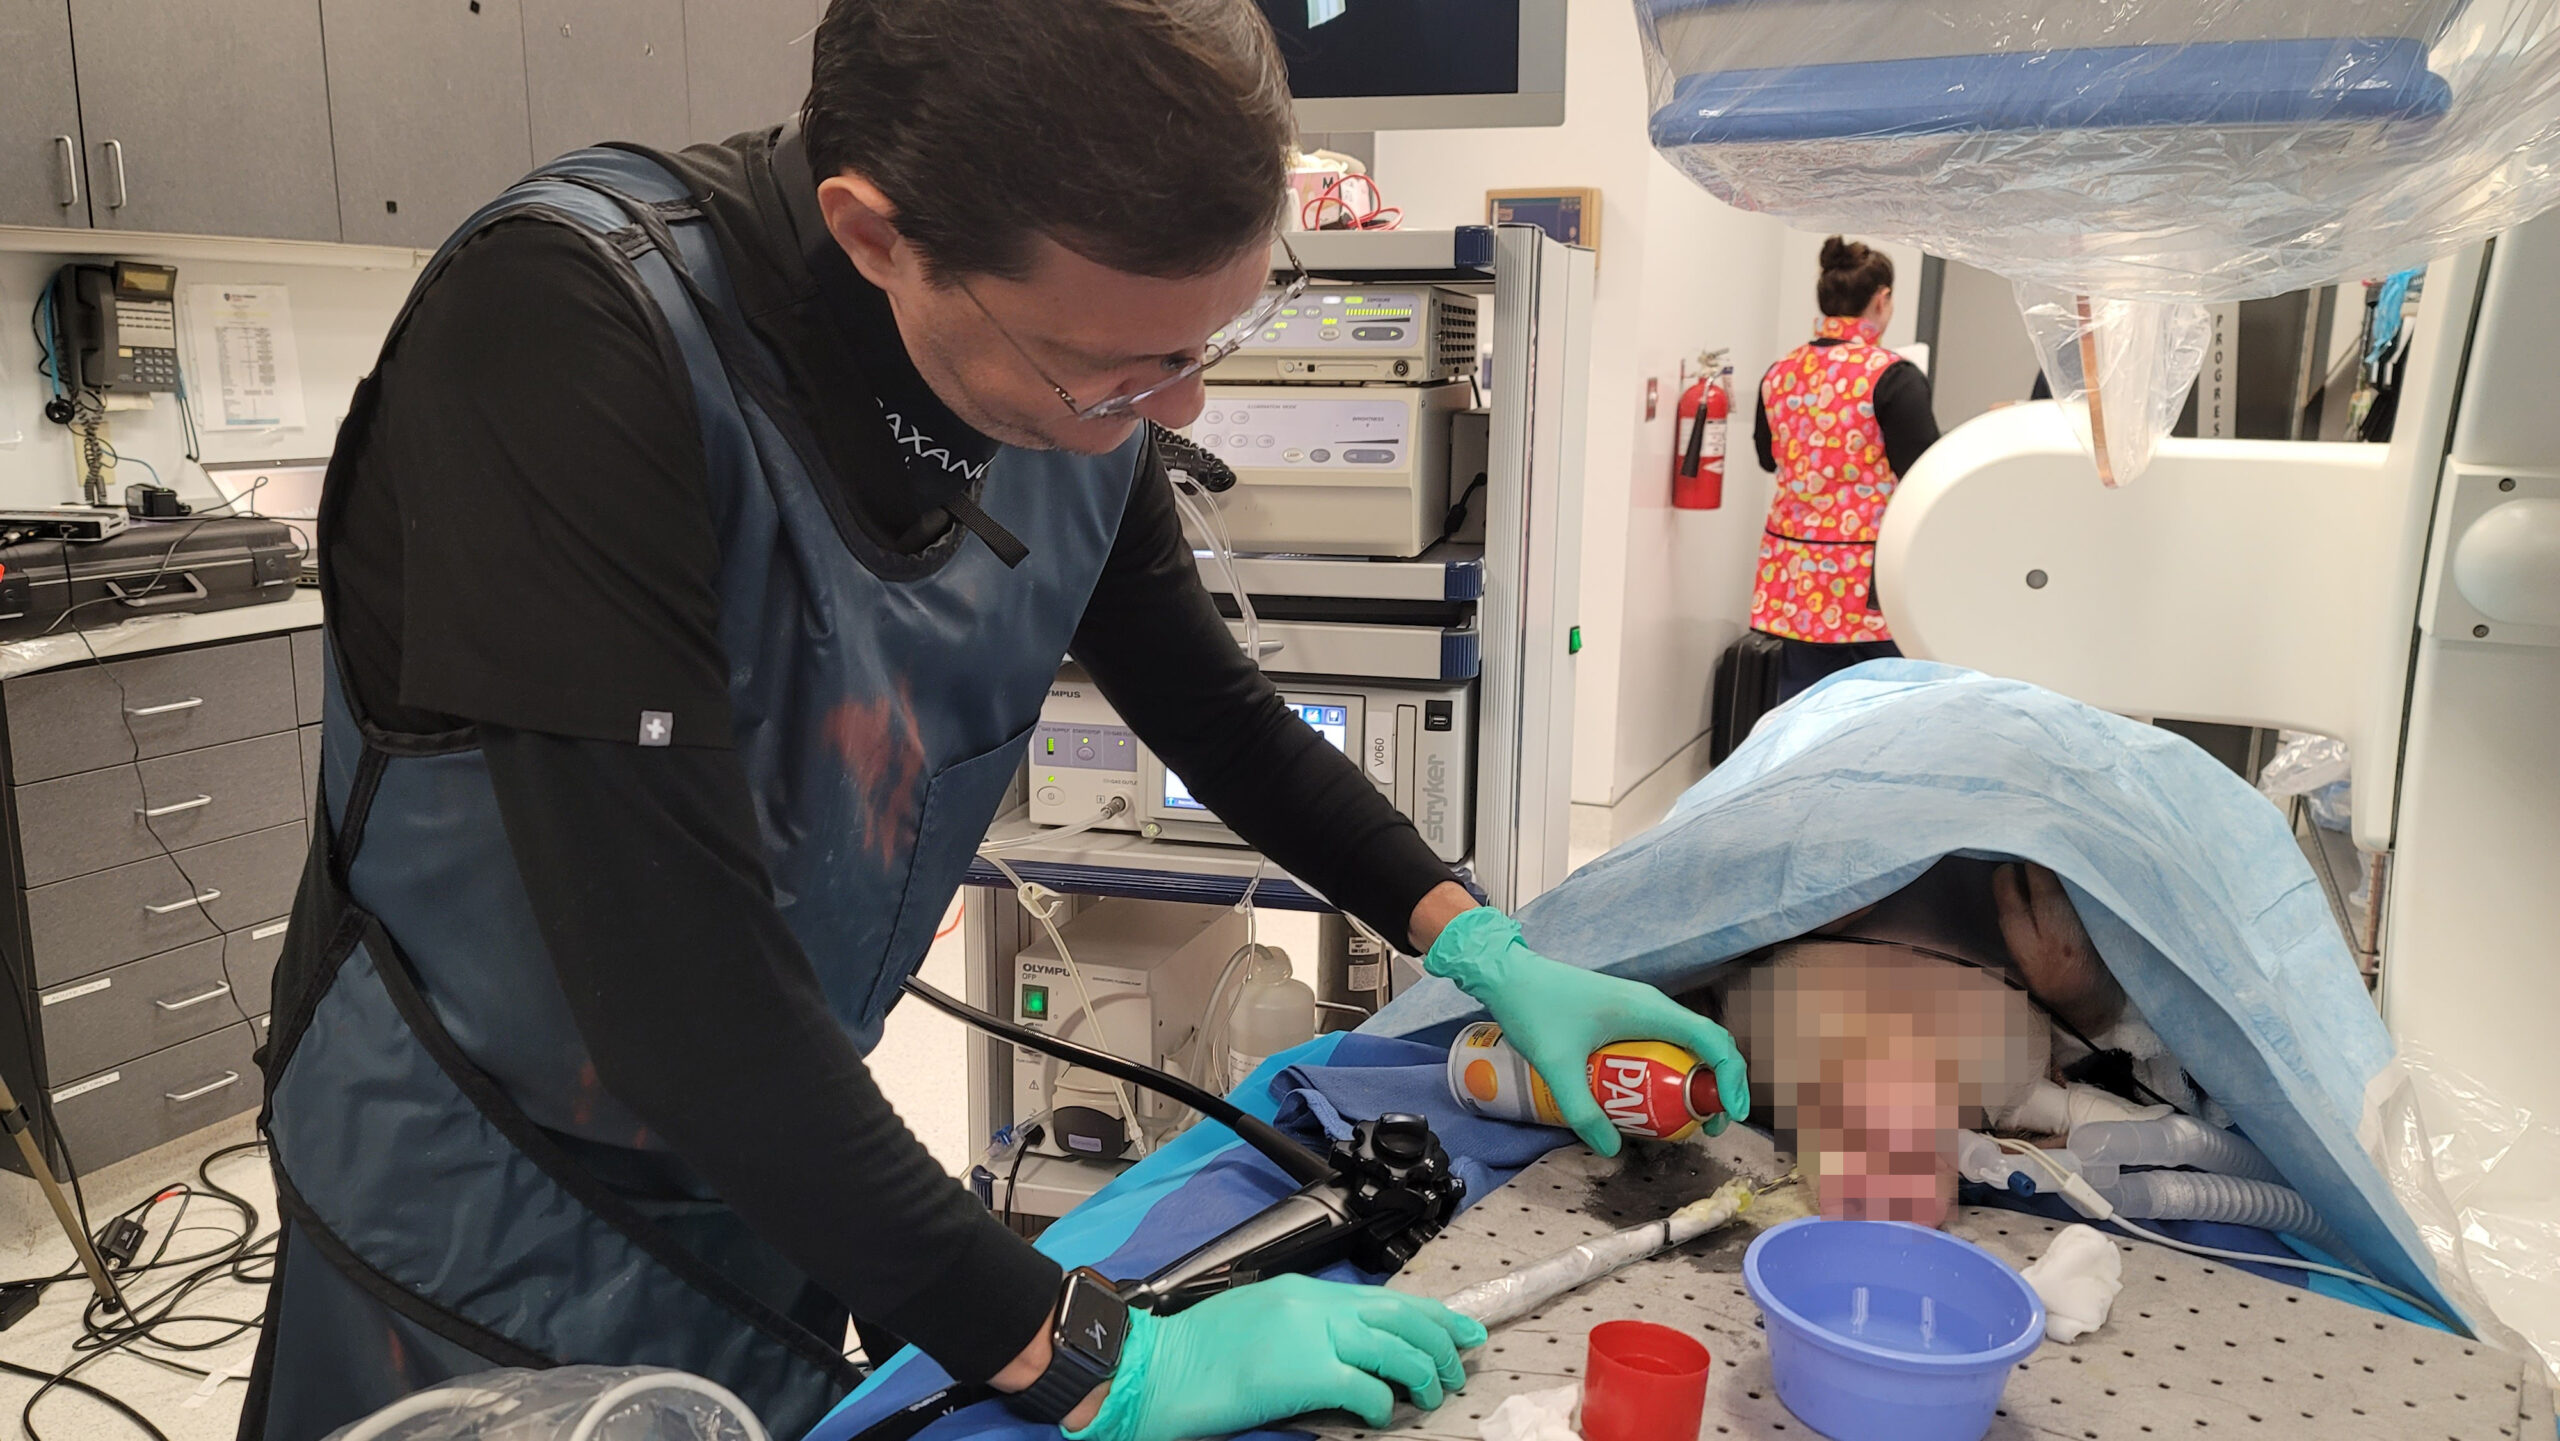

A fully incisionless procedure

The first cut-free endoscopic treatment for diabesity, ForePass ® is able to replicate the most common types of metabolic surgery (Roux-en-Y Gastric Bypass, RYGB, BilioPancreatic Diversion, and Sleeve Gastrectomy). The first version of our product is aimed at RYGB.

Designed to replicate metabolic surgery without any cuts to internal organs. As effective on diabetes and obesity as metabolic surgery in animals.